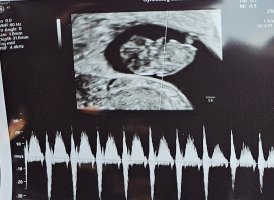

Så fint! Når fikk du satt IVF-termin? Jeg er ferdig hos klinikken og de har jo ikke gitt meg noen termin. UL der gikk veldig fort, så jeg glemte helt å spørre om det.Jubler over ny TUL overstått og alt ser nydelig ut. Målt til 9+2, som er nøyaktig det IVF-termin er satt til.

Fikk høre hjerteslag for første gang! Og lille gullet danset så fint for oss på skjermen![]()